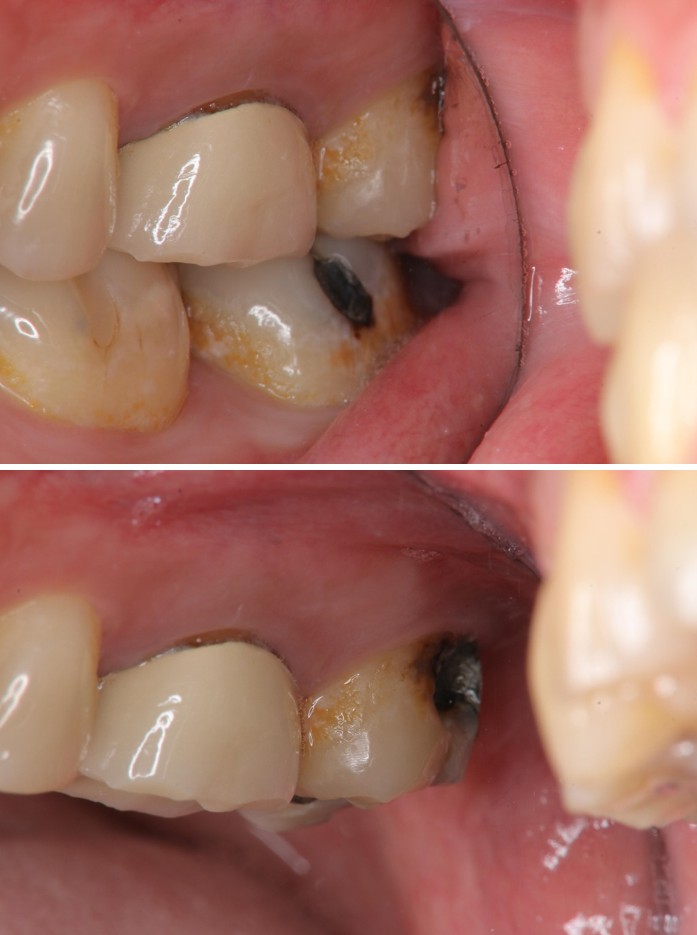

治療前,頰側牙齒蛀牙